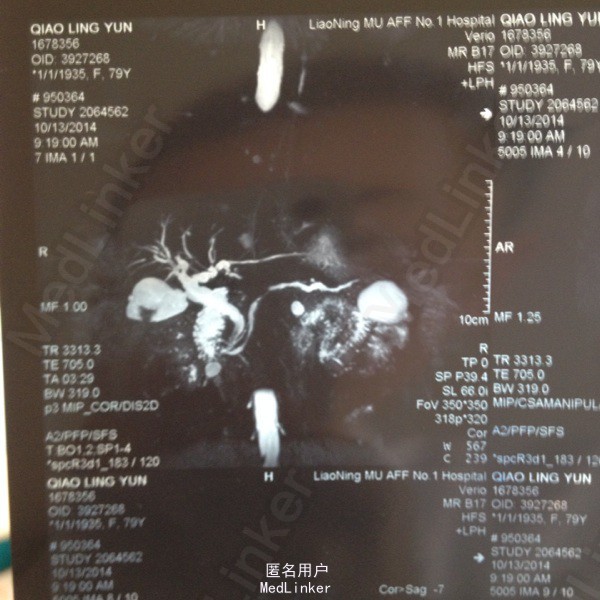

79岁女患,右上腹不适一年。无发热,无噁心及呕吐,无腹泻腹痛。 在普外轮转收集的片子,只有此患者图片,根据此图片回忆的患者病史及查体。时间较长,可能不详尽。

查体:右上腹轻压痛。余未见异常。 MRCP:见图片, 只有此患者图片,根据此图片回忆的患者病史及查体。时间较长,可能不详尽。

胆囊结石。 行腹腔镜胆囊切除术。

MRCP多么清晰,美丽。自己收集了一些基本疾病片子及特殊片子。以后虽然不看或看的机会很少,但收集过程也是一个学习的过程。